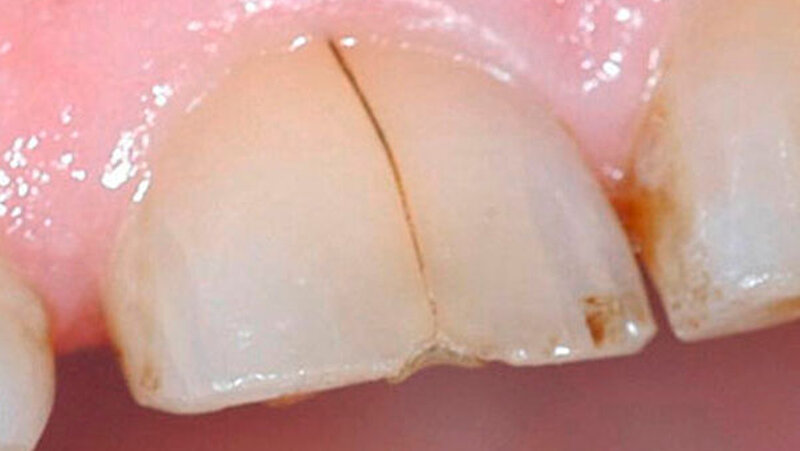

Bei der Vorstellung in der Poliklinik zeigte sich klinisch eine Schmelzfraktur auf der bukkalen Fläche des Zahns 11 (Abbildung 1). Die Messung der Taschensondierungstiefe (TST) ergab an dieser Stelle lokal begrenzt einen Wert von 7 mm (Abbildung 2). An allen übrigen Messpunkten lag eine physiologische TST von 3 mm vor.

Während die palatinale Fläche unbeschädigt war, zeigte die bukkale Fläche eine vertikale Frakturlinie (Abbildung 3), die mit einem feinen diamantierten Schleifkörper erweitert wurde (Abbildung 4). Zusätzlich erfolgte die Entfernung des retrograden Wurzelkanalfüllmaterials. Beide Defekte wurden mit Biodentine (Septodont, Niederkassel) aufgefüllt (Abbildung 5).